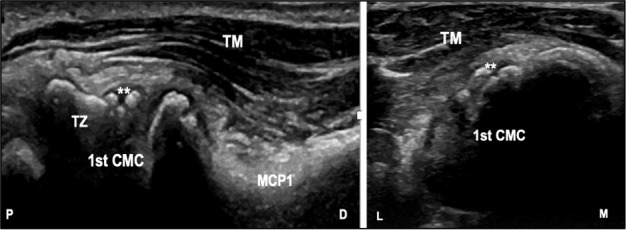

Background: Osteoarthritis is a debilitating degenerative disease more pronounced in elderly affecting many joints. The first carpometacarpal joint (CMC1) is commonly affected. Pain is the major complaint, which can impact patient's daily activities. Intra-articular glucocorticoid injection can be considered if conservative measures fail and ultrasound guided injection might be superior to the traditional anatomic landmark-guided technique. Objective: The aim of this study is to evaluate the effectiveness of ultrasound-guided versus landmark-based approach to intra-articular CMC1 injection using the Australian Canadian osteoarthritis hand index (AUSCAN). Methods: Adult patients diagnosed with symptomatic CMC1 osteoarthritis who failed conservative measures were enrolled. In this prospective observational cohort study, utilizing a convenience sample, intra-articular corticosteroid injection was administered either by ultrasound-guided technique or landmark-based approach. Pain, stiffness and function in 10-points scale at baseline, 6 and 12 weeks were collected and analyzed using descriptive analysis. Results: There were 33 patients enrolled. Mean age was 63 years, with females making up the majority of participants (n = 28, 84.8%). Mean duration of CMC1 pain was 10 months (SD=2.5) up to the point of receiving the injection. Ultrasound guided injection was performed in 60.6% (n=20), while 39.4% (n=13) had the landmark approach. Both groups achieved a statistically and clinically significant level of change in AUSCAN score at week 6 (P≤ 0.05) but with a recurrence of symptoms at week 12 (P ≤ 0.05). At both intervals the AUSCAN scores were better than baseline (P ≤ 0.05). There was no difference between the two groups regarding baseline pain VAS score (mean ultrasound group= 6.6 vs landmark group= 7.5; P = 0.18). No significant differences were identified between two groups in terms of changes from baseline to 6, 12 and between 6 to 12 weeks in pain, stiffness and hand function (P > 0.05). Conclusion: No difference was found between the ultrasound-guided and landmark-based approaches for CMC1 injection on pain score, stiffness, or function.